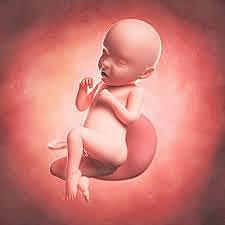

• Semana 20

35

Semana 20

el lanugo cubre todo el cuerpo

aparecen las cejas y las pestañas

aparecen las uñas en pies y manos

el bebé es más activo con mayor desarrollo muscular

la madre puede sentir al bebé moviéndose

los latidos cardíacos fetales se pueden escuchar con un estetoscopio